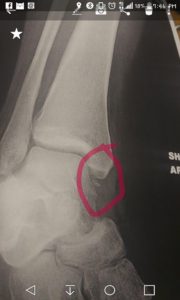

The doctor returned in a little bit with a printout of my x-ray. “Have you previously injured your ankle?”

Confused. “No?”

He gave me a sympathetic look and handed over the x-ray. “I’m afraid it’s a fracture.” He showed me the little chip of bone that had broken away.

That turned out to be a ridiculously short appointment, because there was precisely fuck all we could do about the break, turns out. I had essentially sprained my ankle SO BADLY it pulled a chip of bone away. The chip was too small to screw back in without it disintegrating, so no surgery needed, and the damage was in such a spot that a cast would be useless. I was given a brace that hurts like the devil to wear and told to elevate, ice, medicate, until I felt like I could put weight on it.